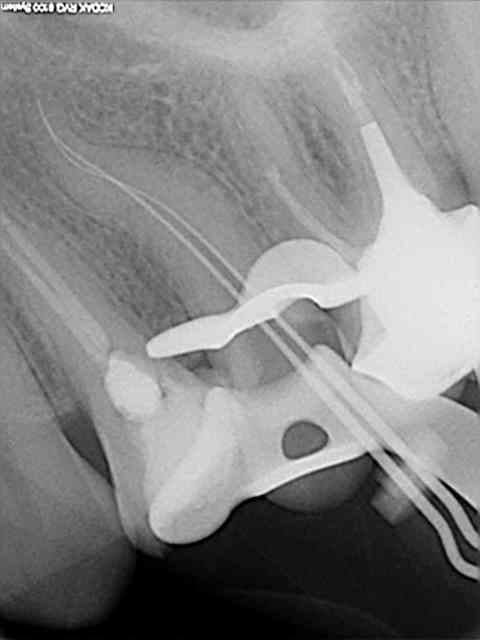

Tiens en parlant d'honneur la je meriterais un grand doigt.

Protaper dans la racine mesiale, amlg dans la racine distale, Mais j'ai mis la digue :p.

Conclusion RAS au controle a 1 an !

Comme dit Stéphane tous les moyens sont bons tant qu on arrive au résultat escompté ;p